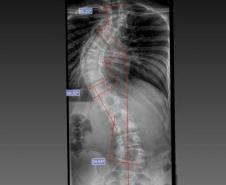

Laura era portadora de escoliose e, em agosto de 2025, realizou a cirurgia de correção da coluna, o que lhe permitirá ter uma vida normal de agora em diante. Moradora de Bom Sucesso do Sul, região Oeste do Paraná, é acostumada a andar a cavalo, mas com o problema na coluna a prática estava longe de ser prazerosa.

A cirurgia ocorreu no dia 28 de julho e uma segunda etapa em quatro de agosto. Desde então, Joyce viu a sua vida mudar. “Nasci com a escoliose e tinha muita dificuldade e limitações para caminhar e perda de movimento. Havia dias em que eu não levantava da cama. Quando saia de casa recebia olhares de julgamento das pessoas, que era o que mais me incomodava. Depois da cirurgia, posso dizer que eu tenho uma nova vida. Eu venci a batalha”, relatou.

O médico João Elias explica que a escoliose é um termo usado para quando você olha a coluna e percebe uma curvatura. Pode acontecer por várias causas, desde uma escoliose congênita, quando o bebê nasce com uma vértebra mal formada e essa vértebra vai levando ao desenvolvimento de uma deformidade na coluna; a neuromuscular, causadas por doenças neurológicas ou musculares, como uma paralisia cerebral, até as idiopáticas, causadas por alterações genéticas e que podem se desenvolver apenas na adolescência.